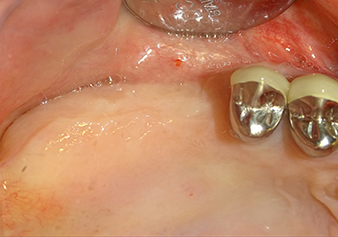

Preoperative findings: The alveolar ridge has healed well, including sufficiently broad, keratinised gingiva

Fig.1: Preoperative findings: The alveolar ridge has healed well, including sufficiently broad, keratinised gingiva.